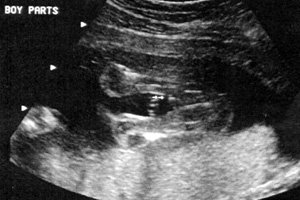

الولد

ولد في الأسبوع ال 15

ولد في الاسبوع ال16